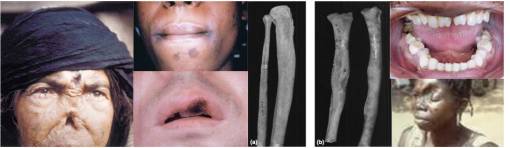

Bejel is caused by Treponema pallidum endemicum. It is most common to arid eastern Mediterranean countries and West Africa. The disease is spread either through direct oral contact or indirectly by eating utensils. The disease first presents as a lesion or patch in the oral cavity, which forms into a raised, eroding lesion. Similar lesions then form on the limbs and trunk. Long term tertiary syphilitic infections known as gummata (pl. gumma) form over time, along with inflammation of the leg bones. The gummata present as a necrotizing area surrounded by a swollen, red area of intense inflammation, with indiscrete edges, and an ulcer-like appearance lacking much granulation or signs of tissue recovery and healing. Long term effects mimic many of those of tertiary syphilis, and include deterioration of tissues in and around the soft tissues of the palate. Penicillin is the treatment for this illness.